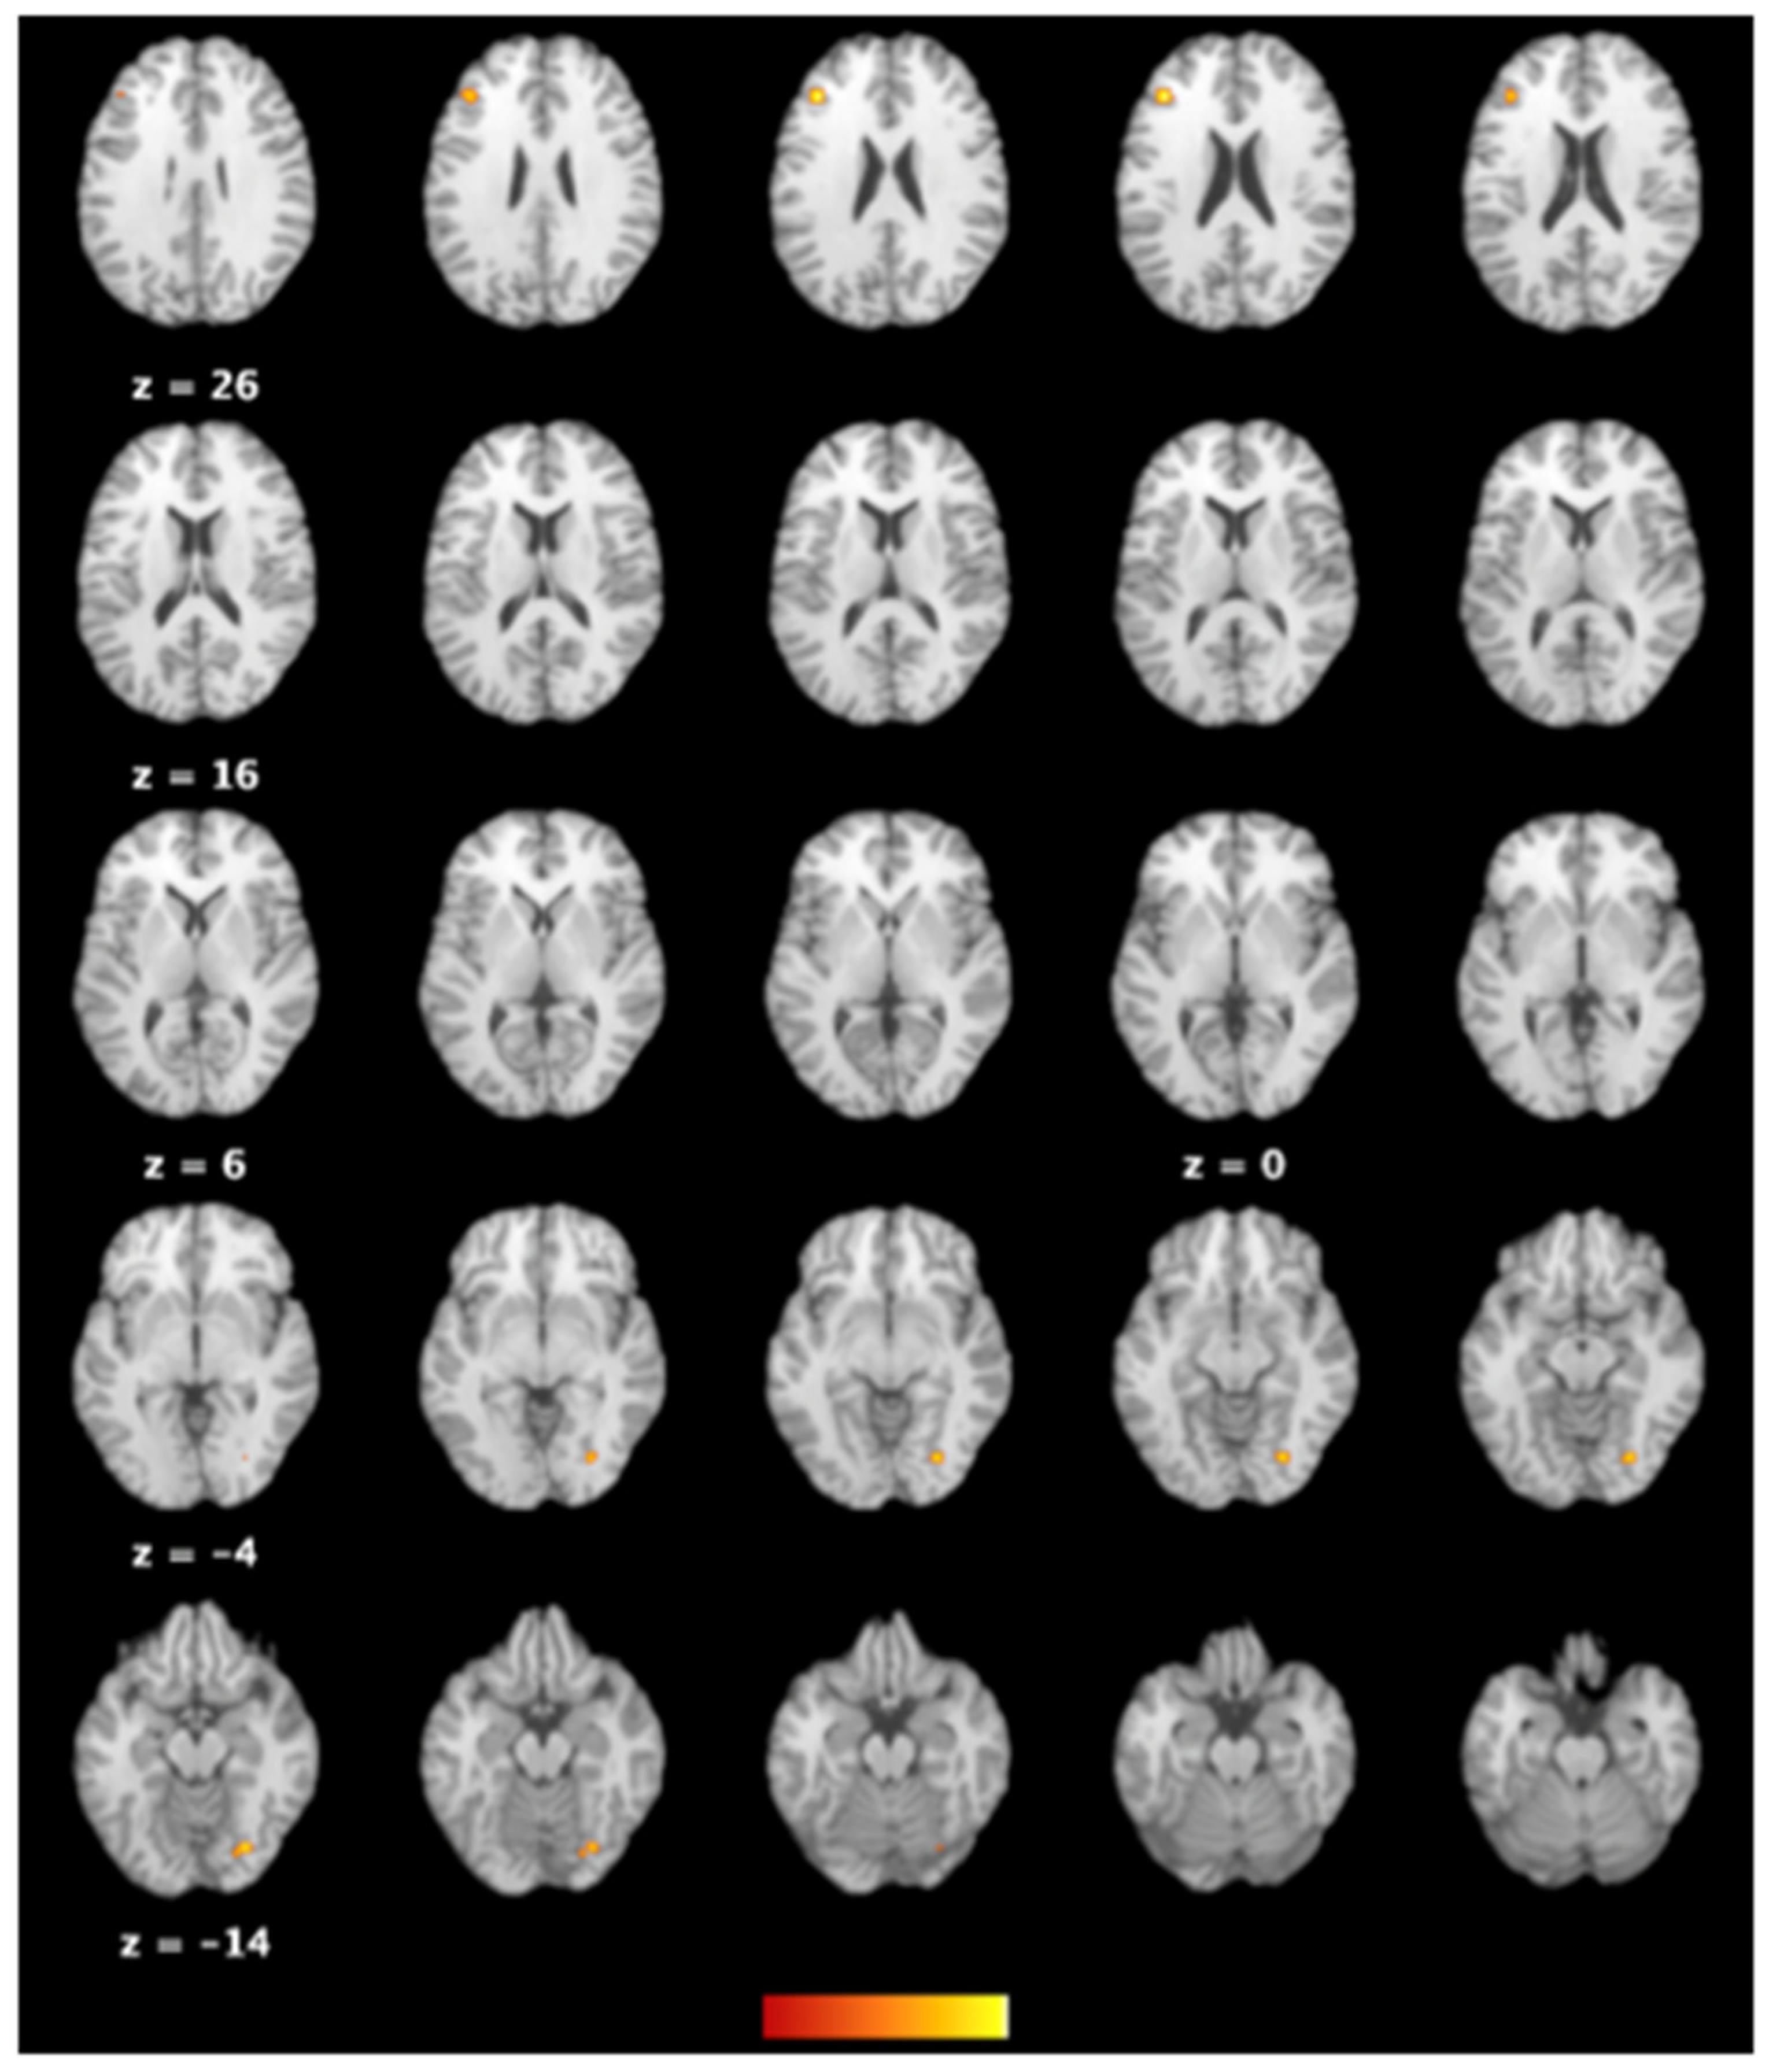

| Cluster | Side | Brain Area | BA | Volume (mm3) | ALE | x | y | z |

|---|---|---|---|---|---|---|---|---|

| 1 | R | Declive of posterior lobe | 568 | 0.014351934 | 28 | −76 | −14 | |

| 1 | R | Lingual gyrus | 18 | 0.014068902 | 28 | −76 | −8 | |

| 2 | L | Middle frontal gyrus | 46 | 472 | 0.016162576 | −38 | 30 | 20 |